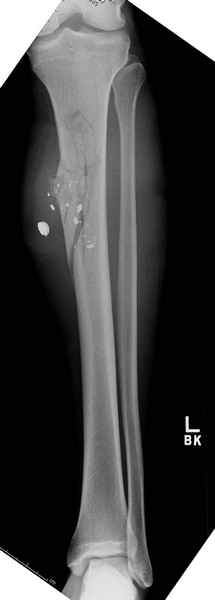

3 такие раны после удаления пули и остатков одежды можно закрыть первично